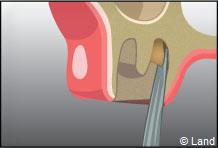

L’intervention commence là aussi par une anesthésie locale, puis le chirurgien-dentiste procède à une incision de la gencive et à un dégagement du tissu osseux autour de la dent.

Parfois cette dernière est sectionnée pour ne pas traumatiser l’os souvent responsable de suites opératoires douloureuses.